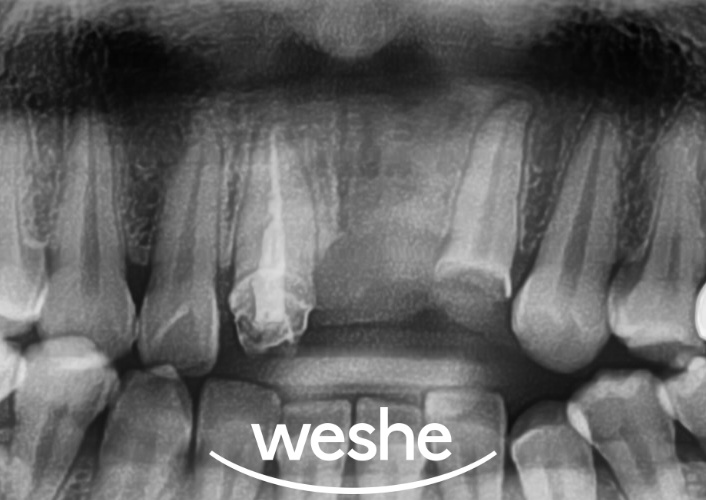

초진

20250604

마곡역 치과 에서

준비한 예시 사진을 보면

앞니 부위 브릿지 보철이 탈락된 상태입니다.

브릿지는 양쪽 치아를 지대치로 활용하여

중간의 빠진 치아 공간을

채우는 보철 방식입니다.

11번과 22번 치아가 지대치로 사용되어

21번(상실된 치아)을

대체하고 있습니다.

탈락 원인을 확인하기 위해

엑스레이 검사를 진행합니다.